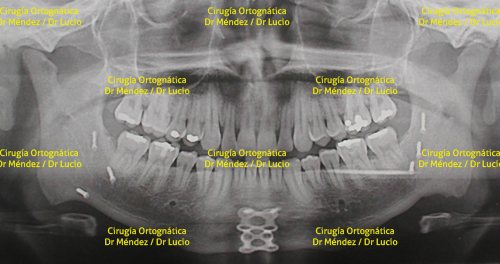

El Dr. Andrés Méndez conjunta habilidades y conocimientos con el Dr. Ernersto Lucio, para realizar procedimientos de cirugía ortognatica. Los siguientes son algunos de los casos operados.

HIPOPLASIA MAXILAR Paciente operado de avance maxilar |